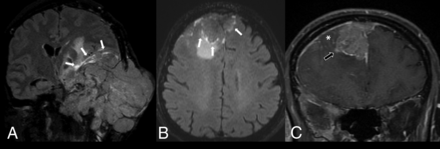

Recent studies suggest that malignant dural-based masses receive vascular supply from various branches of the internal and external carotid arteries according to their cell types and locations.14⇓-16 No pial vascular supply in the tumor capsule has been described for malignant dural-based masses. However, our study demonstrated 2 cases of malignant dural-based tumors (dural metastasis of squamous cell carcinoma and mucoepidermoid carcinoma) with complete rim enhancement on the CE-FLAIR sequence accompanied by aggressive imaging features, including adjacent leptomeningeal enhancement and brain parenchymal invasion. The CE-FLAIR rim sign of these lesions could be related to prominent pial arterial supply at the peripheral portion of the tumors (Fig 3).

A, Anaplastic meningioma (WHO grade III). CE-FLAIR (A) sequence demonstrates a large extra-axial mass with cortical breakthrough involving the left middle skull base and left temporal skull with the CE-FLAIR rim sign (white arrows). Malignant soft-tissue tumor was the favored diagnosis in the initial report. The pathologic result is anaplastic meningioma (WHO grade III). A malignant dural-based mass on CE-FLAIR (B) and CE-T1WI fat suppression (C) sequences shows an extra-axial heterogeneously enhancing mass at the bilateral frontal convexities that had invaded the anterior-superior sagittal sinus and demonstrates the CE-FLAIR rim sign (white arrows), accompanied by focal leptomeningeal enhancement (asterisk) and adjacent brain parenchymal invasion (black arrow). Meningioma was the favored diagnosis in the initial report. The pathologic result was metastatic mucoepidermoid carcinoma.

The presence of cortical breakthrough in dural-based masses represents an aggressive feature with significant bone destruction, which is supposed to be found in malignant dural-based tumors and WHO grade III meningiomas and is very unusual in WHO grade I meningiomas.2 Our study found that cortical breakthrough had moderate sensitivity, high specificity, good PPV and NPV, and the highest accuracy for consideration of malignant dural-based tumors, similar to the results of Starr and Cha.2 However, there were 5 cases of meningiomas that demonstrated cortical breakthrough. All were anaplastic meningiomas (WHO III) with complete rim enhancement on CE-FLAIR sequences, features that could help suggest anaplastic or malignant meningioma rather than malignant dural-based tumors (Fig 3).